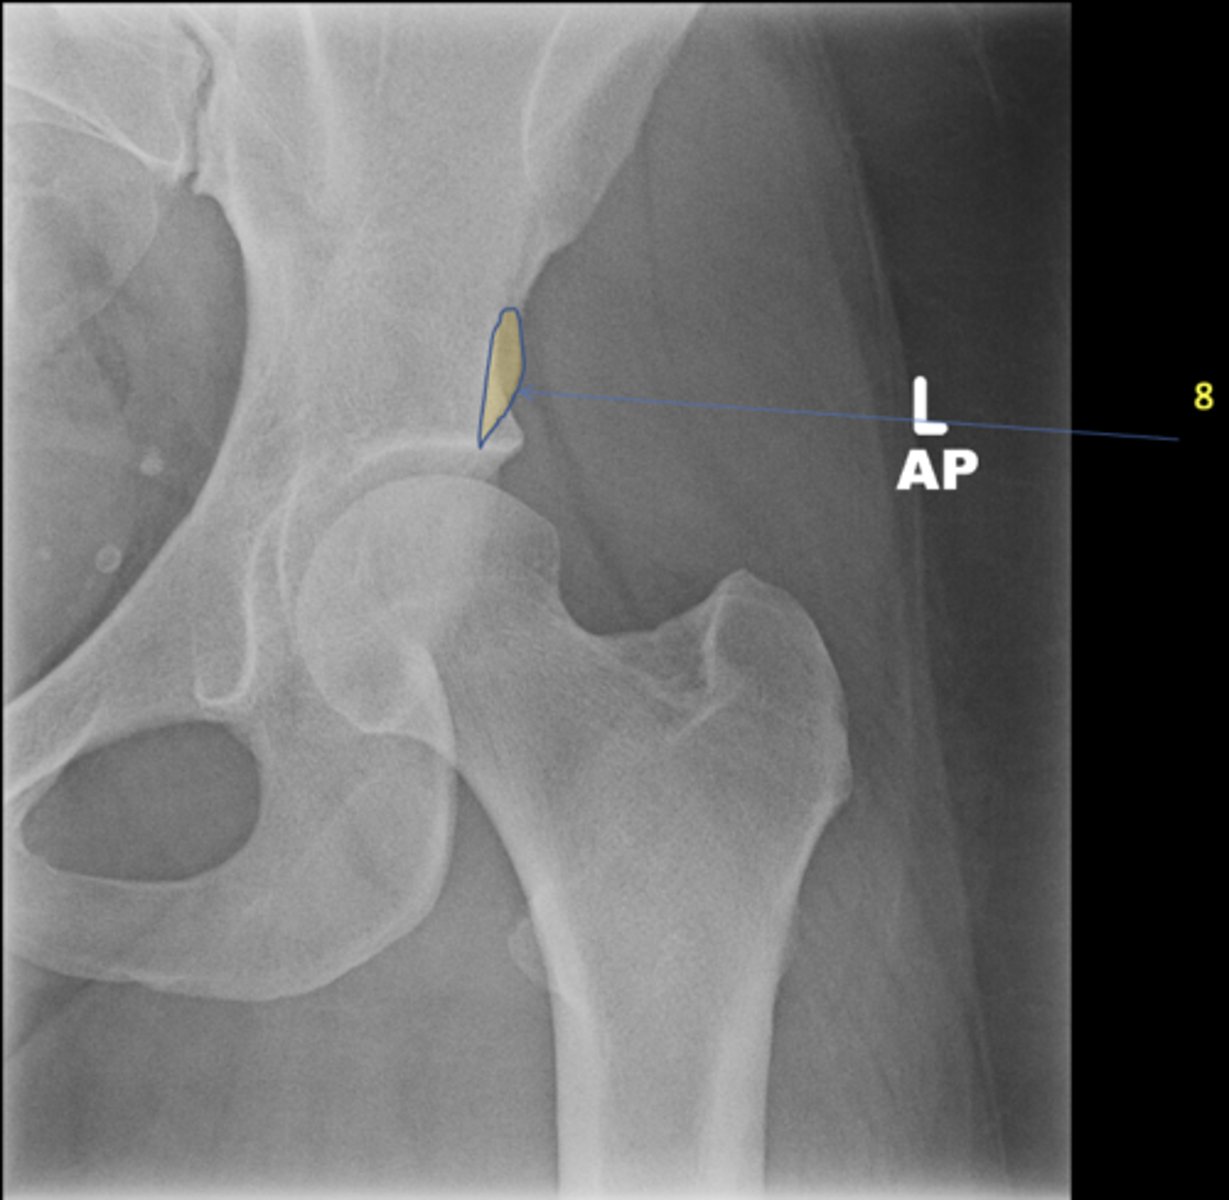

Left frog-leg hip

View?

Acetabulum

ID 1

Greater trochanter

ID 2

Lesser trochanter

ID 3

Femoral head

ID 4

Ischial spine

ID 5